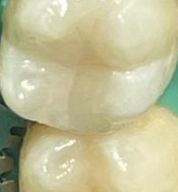

7 работ в портфолио